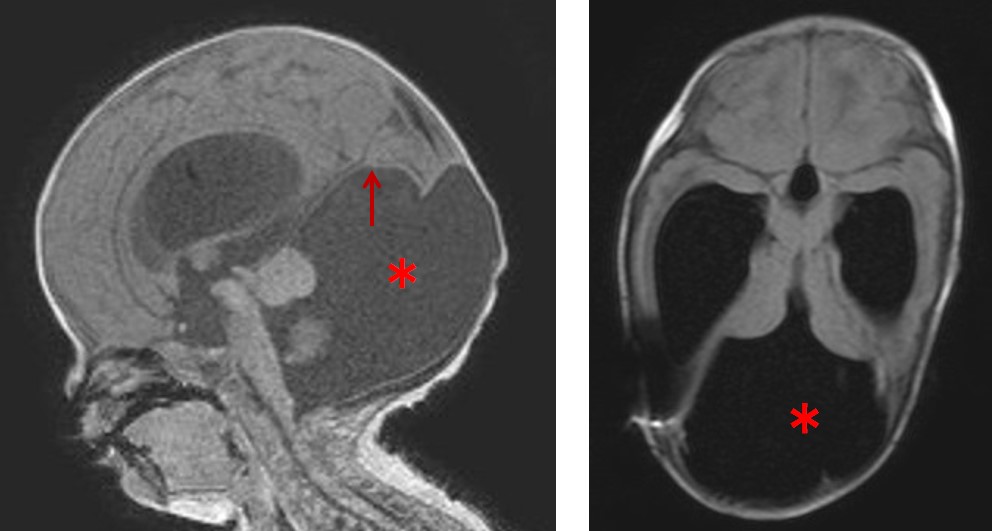

図1:ダンディ・ウォーカー症候群のMRI

小脳虫部の低形成、第四脳室に続く嚢胞(*)、小脳天幕の挙上(↑)、脳室拡大を認める。